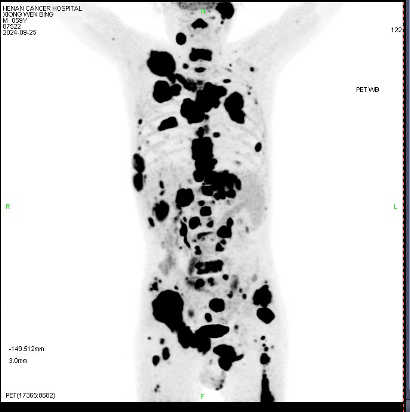

59岁闫先生近一年来经常全身疼痛。当地医院的检查结果显示,他的癌细胞已经转移至身体的多个部位——淋巴、骨骼、肝脏,四处“烽烟”让人不禁想问,这一切的起因在哪里?

(黑**域为活跃的癌细胞)

然而,经过一轮又一轮的检查,各类穿刺活检、基因检测、CT、彩超、磁共振,甚至骨扫描、肠镜、胃镜,病灶竟无处可寻。这让医生们不禁陷入疑惑:癌症的“源头”究竟藏在哪里?